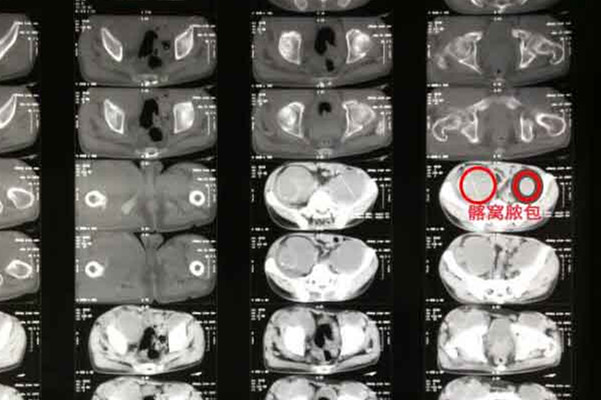

但有些骨结核复发的病情已经发展到非常严重的地步了,则需要考虑手术干预,如脓肿、瘫痪等,通过手术把那些已经被结核病破坏掉的骨头清除干净,在基本切除后的基础上再用其他部位的骨头,比如髂骨植入进去,目的是让植入的骨头和原来即将正常的骨头慢慢长在一起,融为一体。但选择手术需要注意两点,一点是术前术后仍然需要规律的抗结核药物治疗,另外一点就是手术对医院的技术力量要求比较高,如手术医生以及麻醉的情况,设备等等,所以选择手术一定要去正规的大医院。